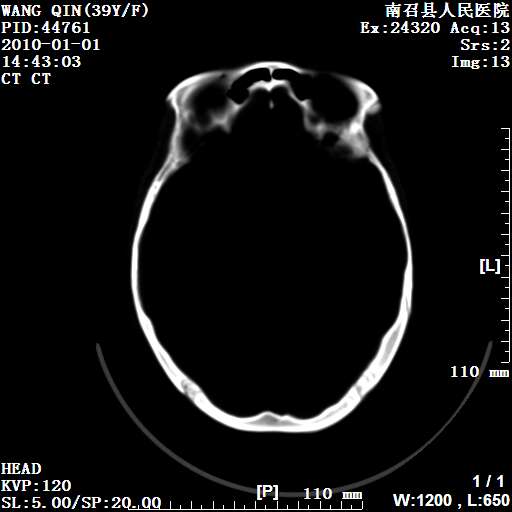

以下是引用随光逐影在2010-1-22 9:03:00的发言:[br]考虑左侧中颅窝(蝶骨翼区)脑膜瘤侵犯蝶骨翼并突入左侧眼眶。

以下是引用水过无痕在2010-1-22 14:55:00的发言:[br]一、定位:颅外占位;二、定性:恶性可能性大;三、组织来源:来源于左侧眼外直肌或其他部位;考虑为:横纹肌肉瘤>转移瘤>脑膜瘤.